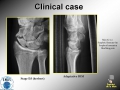

Scaphoid nonunion

Surgical Treatment: vascularized bone graft for scaphoid non union. History of an anatomy